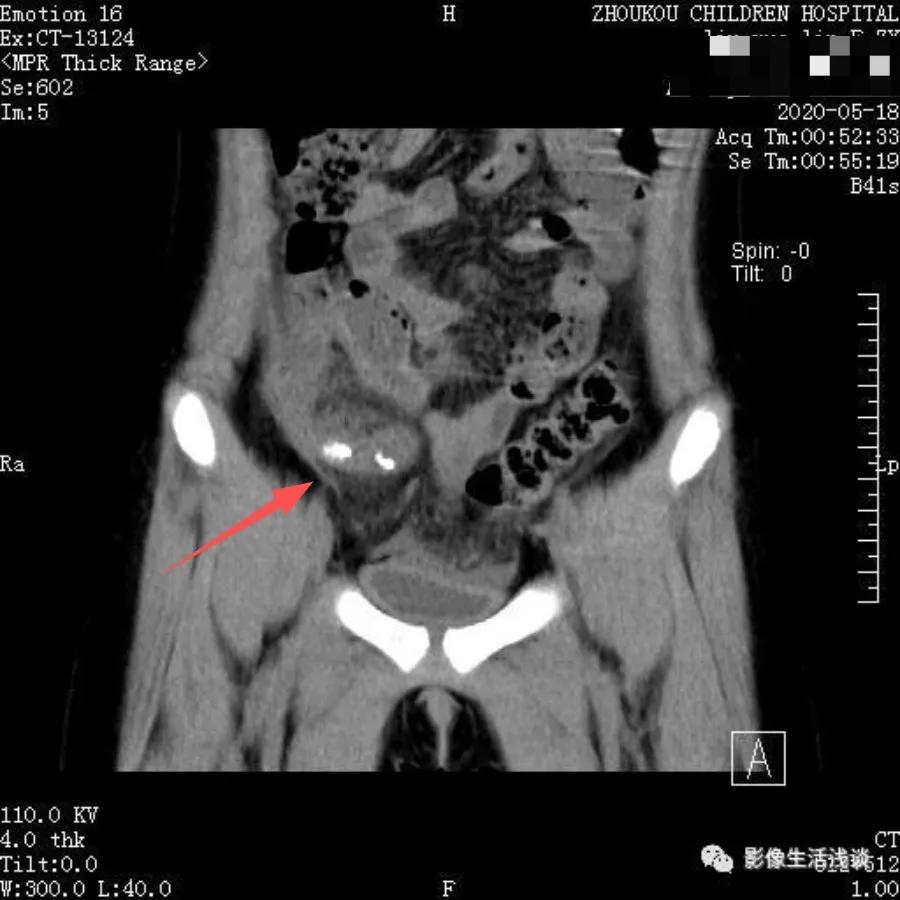

下图是我们工作中常见阑尾炎病例